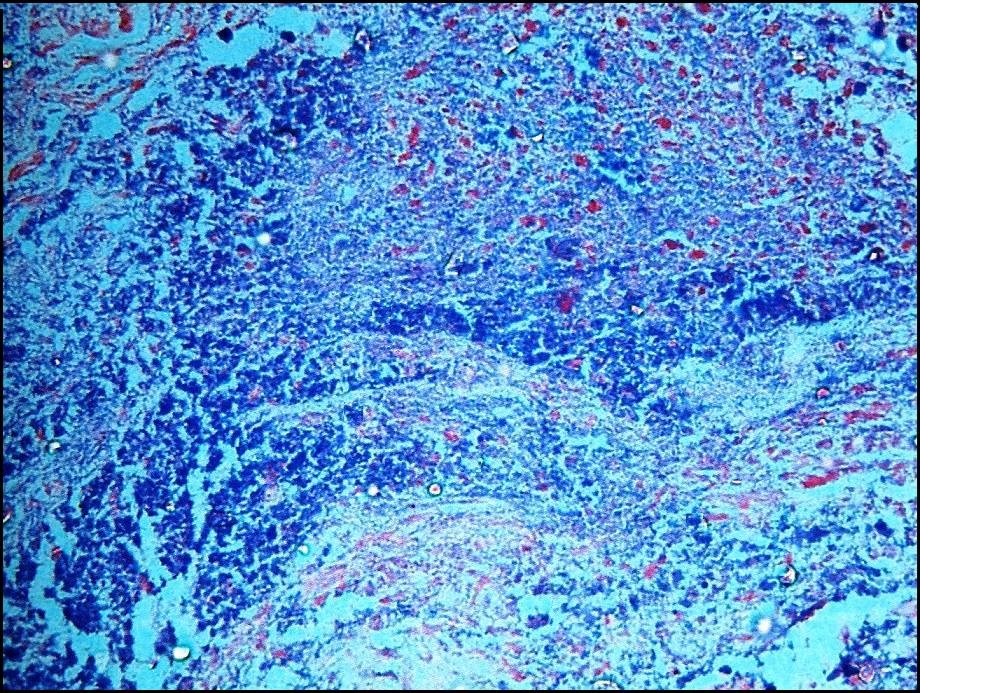

В данном исследовании 25 пациентам с СД были выполнены ампутации конечностей. Язвы конечностей были классифицированы по Вагнеру, выполнена окраска материала по Граму. Также проводилось исследование влажных препаратов, фиксированных гидроксидом калия. Были проведены посевы на кровяной агар, агар МакКонки, декстрозный агар Сабуро и в бульон с сердечно-мозговой вытяжкой, и оценен рост микроорганизмов. Проводилось изучение гистологических срезов с использованием специальных красителей.

В исследовании участвовали 25 пациентов (16 ? мужчин, 9 ? женщин). Возраст пациентов составлял от 30 до 90 лет (средний возраст: 58?10,91 лет). У большинства пациентов были язвы 3-й степени по Вагнеру. Остеомиелит был диагностирован в 13 (52%) случаях: острая форма в 2 (8%) случаях, хроническая ? в 3 (12%) случаях, обострение хронического остеомиелита ? в 8 (32%) случаях. По результатам посевов в большинстве случаев выделялся Proteus mirabilis; на втором месте ? Escherichia coli. В 20 случаях было выделено более одного вида бактерий. Грибы Candida были выделены в 8 случаях; Trichosporon ? в 2 случаях, а Fusarium ? в 1 случае. При гистологическом исследовании Candida были обнаружены у 3 пациентов, а Trichosporon ? у 1 пациента. В 80% случаев остеомиелита наблюдалась полимикробная инфекция.